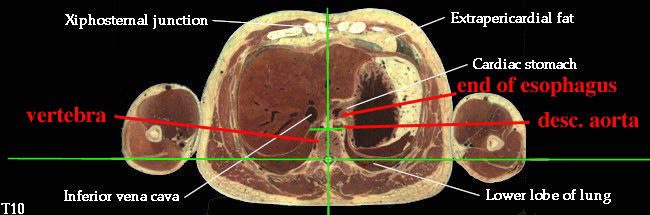

6. Consider the course, relations, constrictions of the esophagus. (N232, TG4-49, TG7-91)The laryngopharynx "becomes" the esophagus at the C6 level. The esophagus passes through the esophageal hiatus of the diaphragm, which is at the T10 level, to end in the cardiac portion of the stomach.

3. Describe the organization of the thoracic sympathetic trunk, in addition to its visceral and splanchnic branches. (W&B 413-416, N158, N160, N165, N209, N240, N254, TG4-45, TG4-46, TG8-03, TG8-14)This set of cross-sections might help (no guarantee!):

- Esophagus: enters the mediastinum a little to the right of the median plane, posterior to the trachea. It passes to the middle of the body, then to the left and anteriorly as it travels down to the stomach. (See "Extra Explanation" below.)